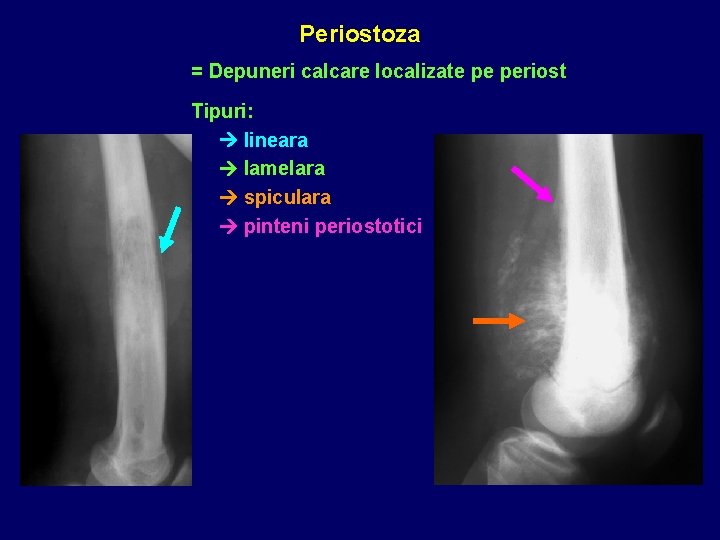

Periostoza = Depuneri calcare localizate pe periost Tipuri: lineara lamelara spiculara pinteni periostotici